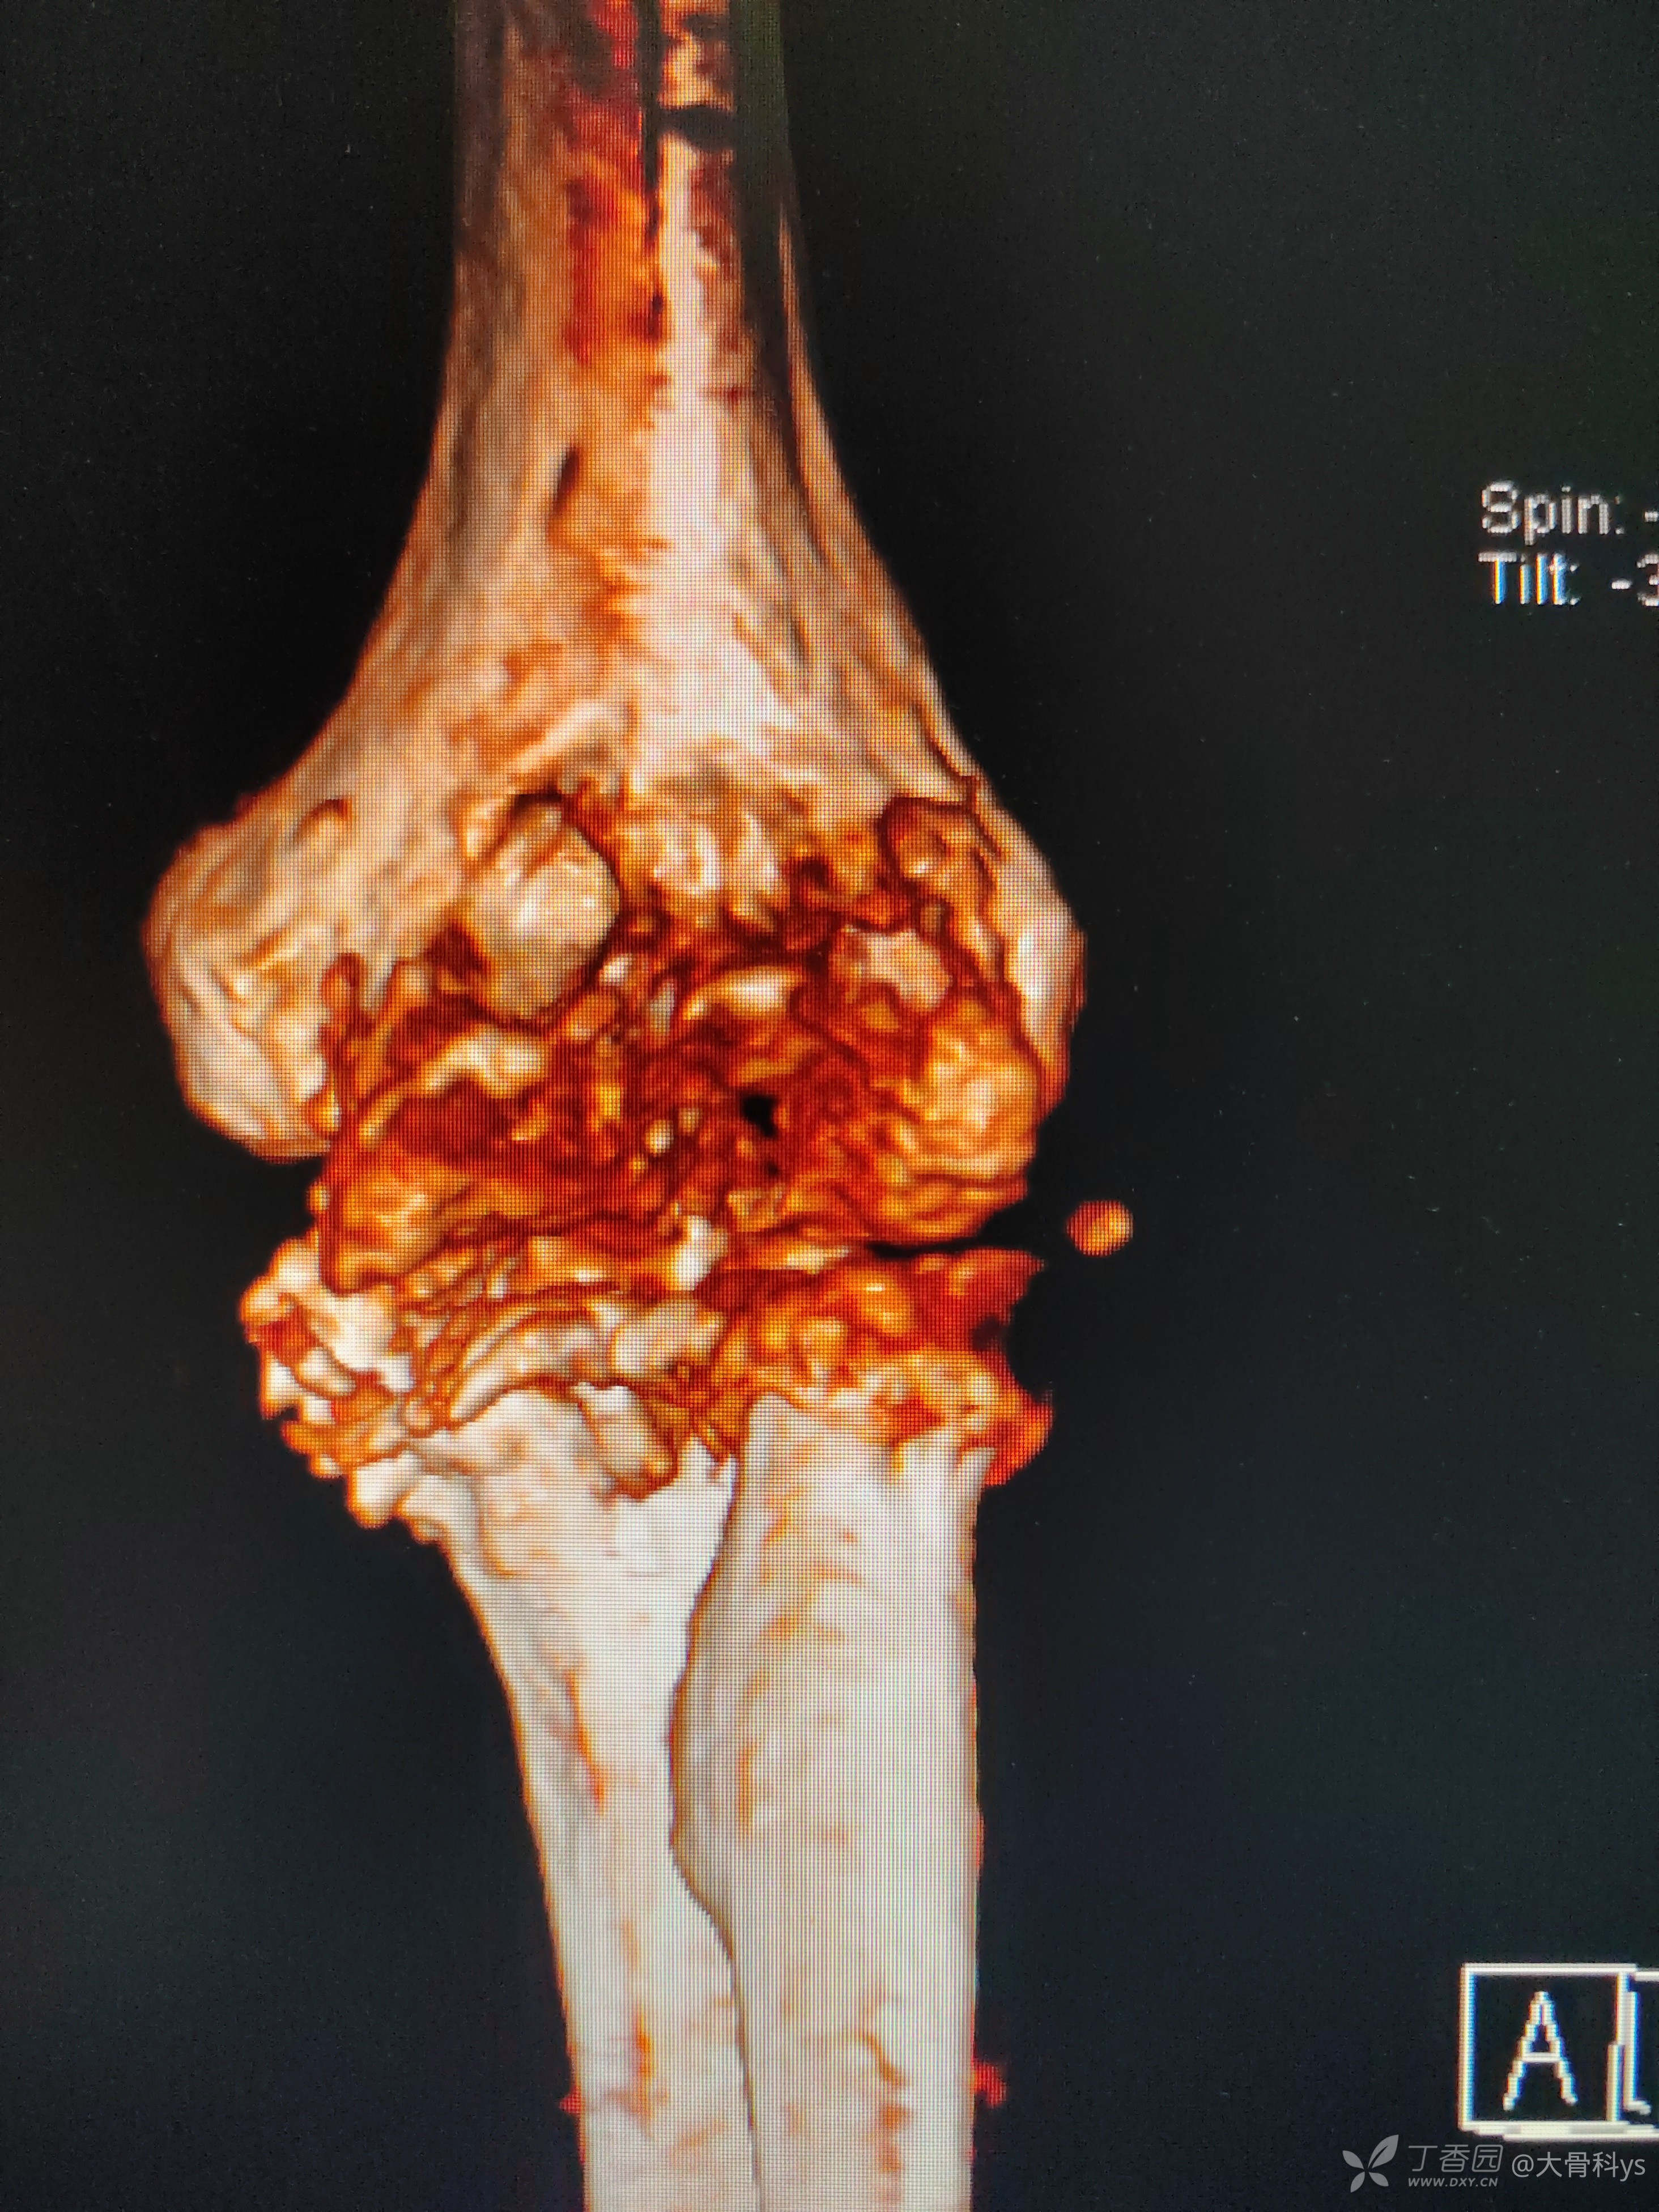

影像学资料

双肺CT检查提示双肺广泛性弥漫性改变:结核?尘肺?

考虑肘关节结核,行关节腔清理+骨髓炎病灶清除+负压封闭引流术。病灶组织再次培养,病灶组织结核杆菌培养,找抗酸杆菌,结核杆菌核酸及利福平耐药检测结果暂未回报。